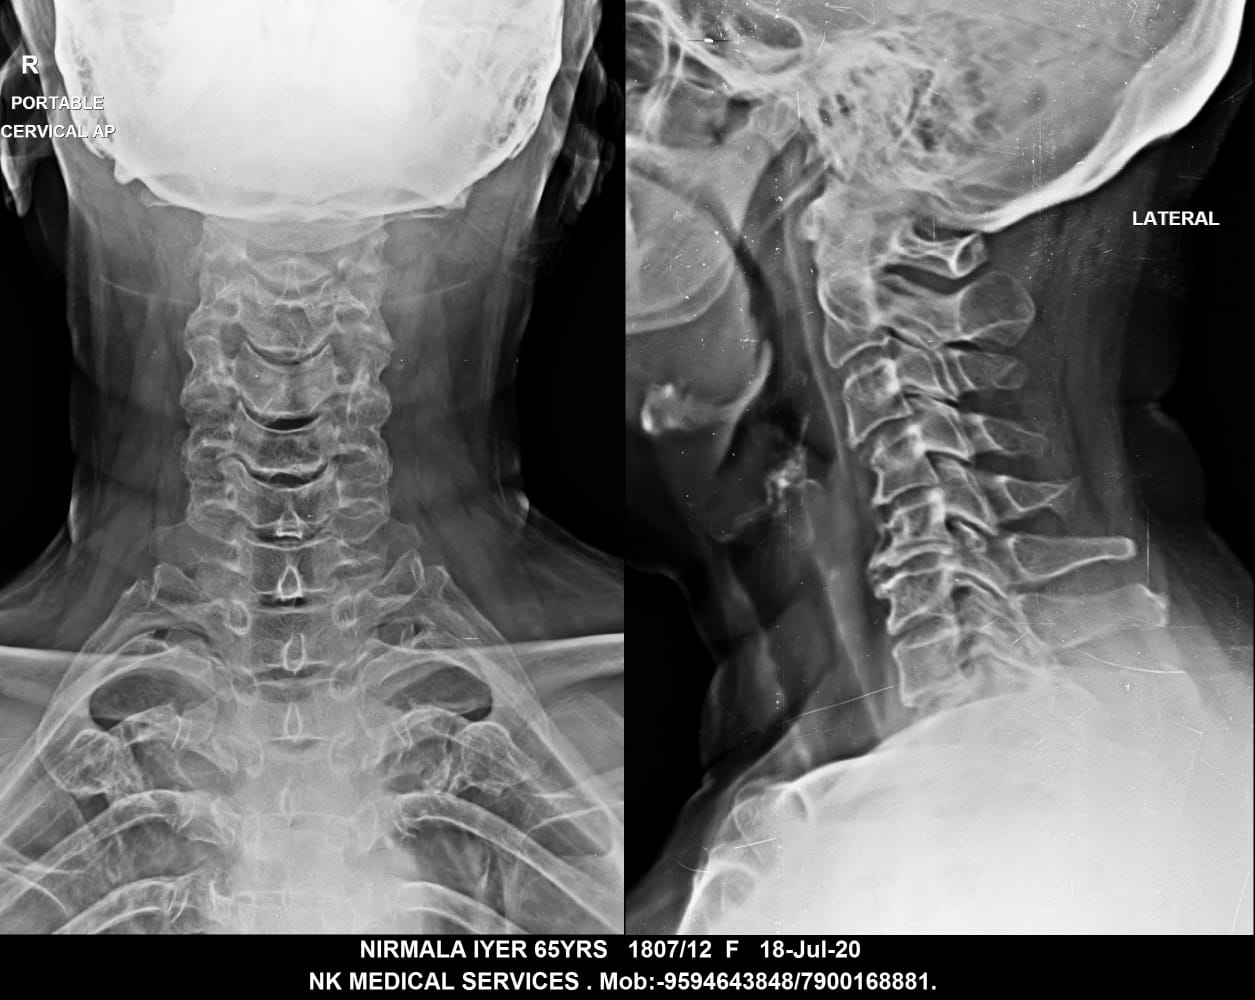

Getwell Urgent Care of Southaven uses digital X-ray technology, which uses less radiation, provides fast turnaround of images, and gives us the ability to manipulate images for more accurate readings. We follow the highest safety standards, with certified equipment and licensed radiology technologists to ensure an excellent image the first time and minimal exposure to radiation. We use digital X-ray to diagnose broken bones, certain lung conditions (e.g., pneumonia), and certain abdominal conditions.